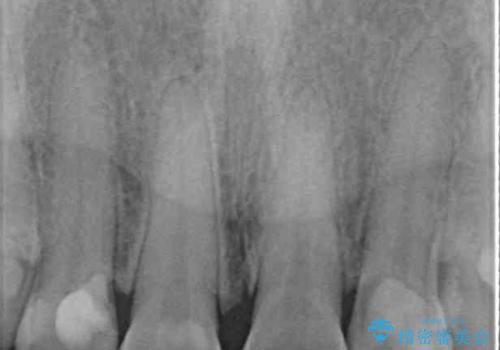

4本とも治療前の歯髄の状態は正常でしたが、補綴治療により歯を大きく削ることになるため、歯髄が炎症を起こすリスクがあることを了解いただきました。